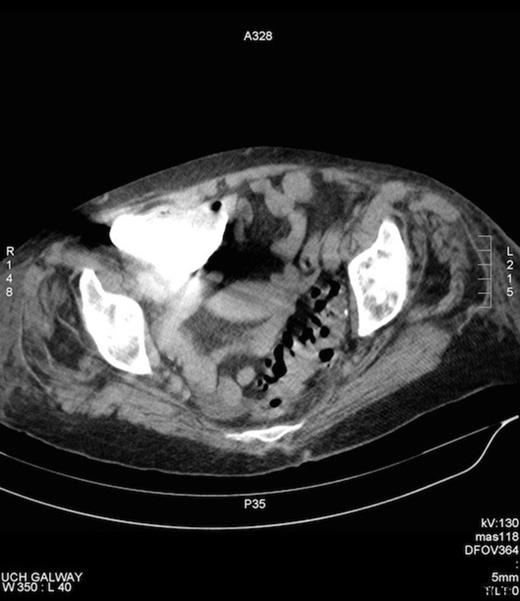

She denied bowel symptoms. Examinations in the SOPD revealed an erythematous, tender swelling in the right groin, with an opening exuding malodorous fluid that had caused marked skin excoriation. On abdominal examination she was tender to palpation in the right groin and guarding and rebound tenderness were absent in the right iliac fossa. There was no clinical evidence of sepsis. A colocutaneous fistula was suspected clinically, when over several days the discharge became faeculent. A CT fistulogram showed a fistulous tract communicating with the caecum and the peritoneal cavity (Figures 1 and 2). She subsequently underwent an elective laparotomy for a planned right hemicolectomy, on a presumptive diagnosis of either a caecal tumour or inflammatory process.

CT fistulogram post injection of contrast via the groin opening. Contrast can be seen to fill the caecum, confirming the presence of a fistula.